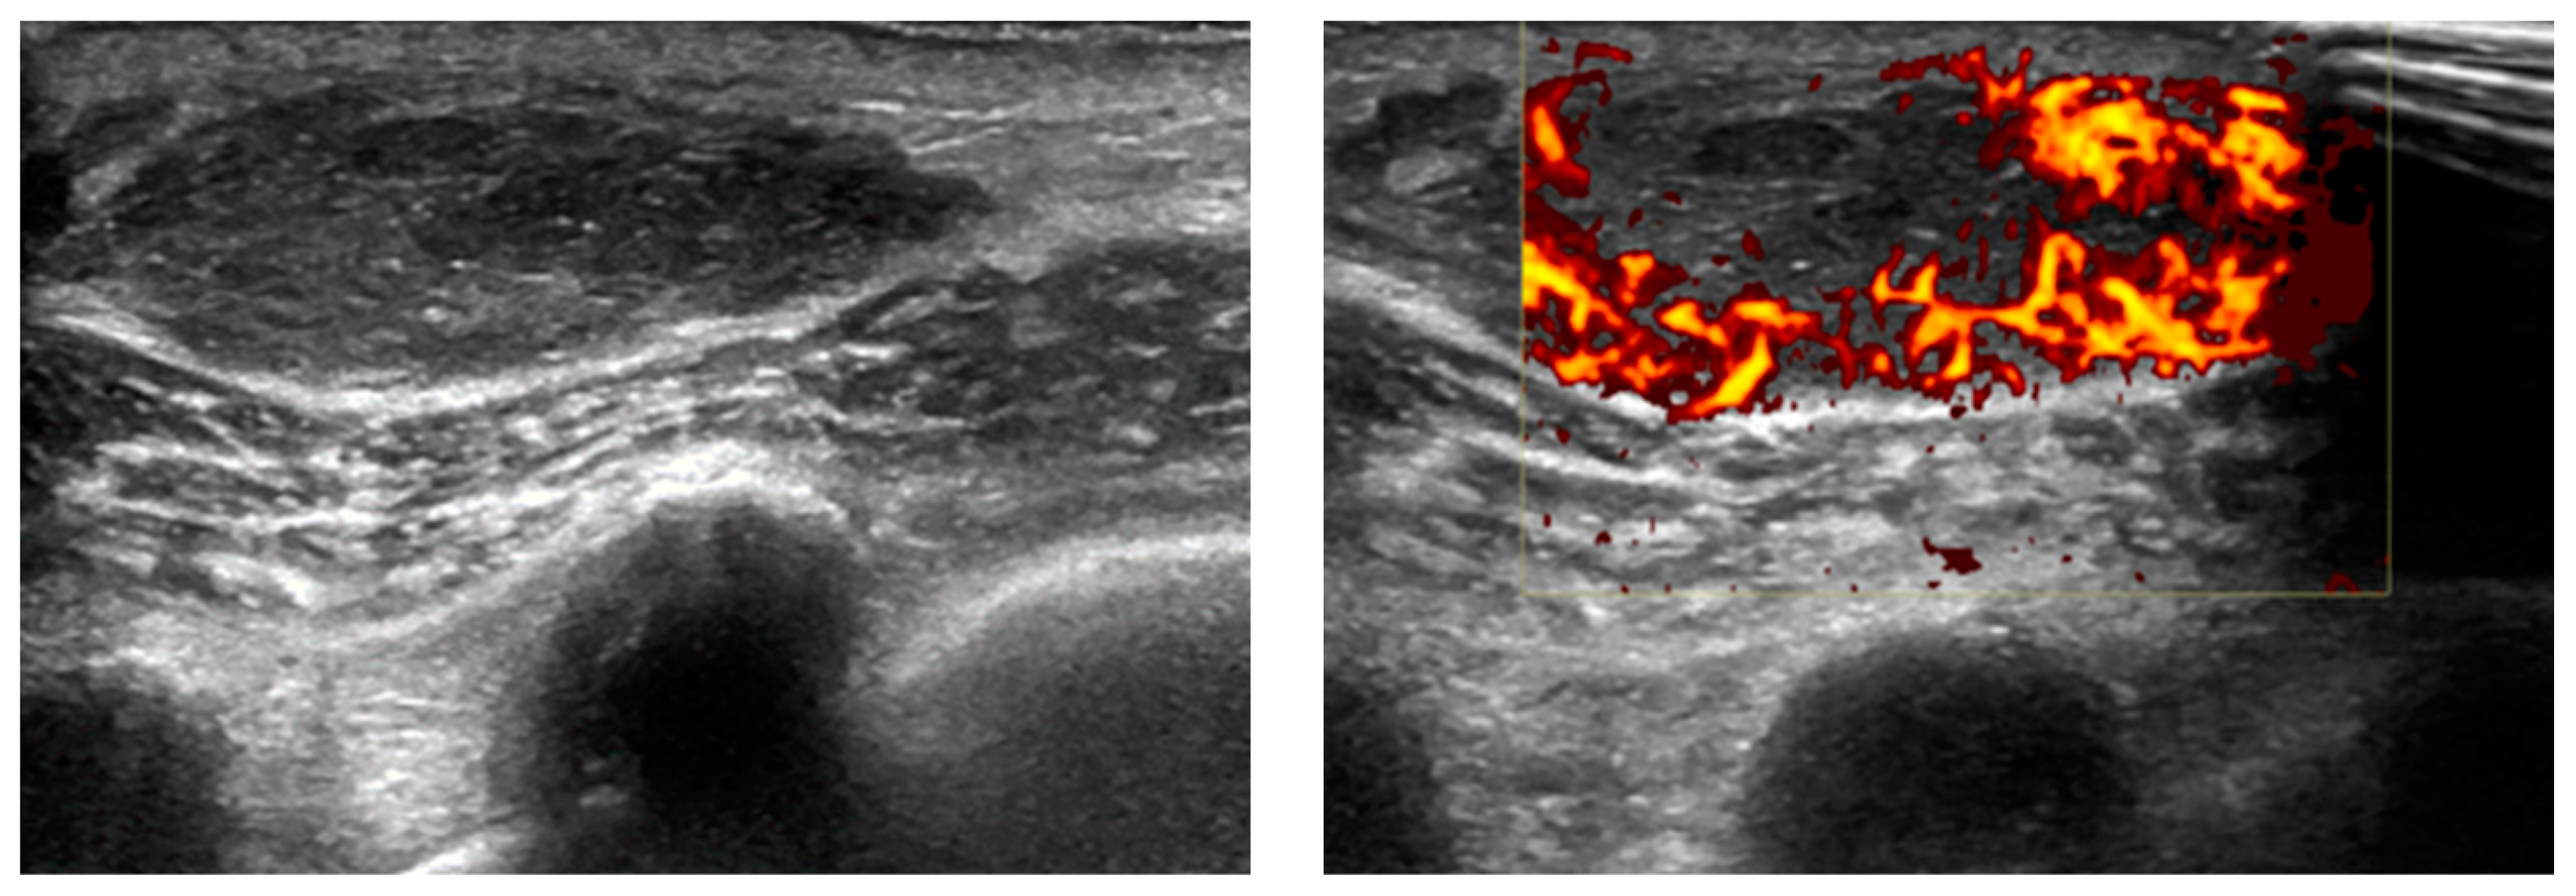

11. Testis

- Bude, R.O. Testicular plasmacytoma: Appearance on gray-scale and power Doppler sonography. J. Clin. Ultrasound 1999, 27, 345–346. [Google Scholar] [CrossRef]

- Bortolotto, C.; Ori-Belometti, G.; Rodolico, G.; Draghi, F. Plasmacytoma of the testis in a patient with previous multiple myeloma: Sonographic appearance. J. Ultrasound 2016, 19, 153–155. [Google Scholar] [CrossRef] [PubMed]